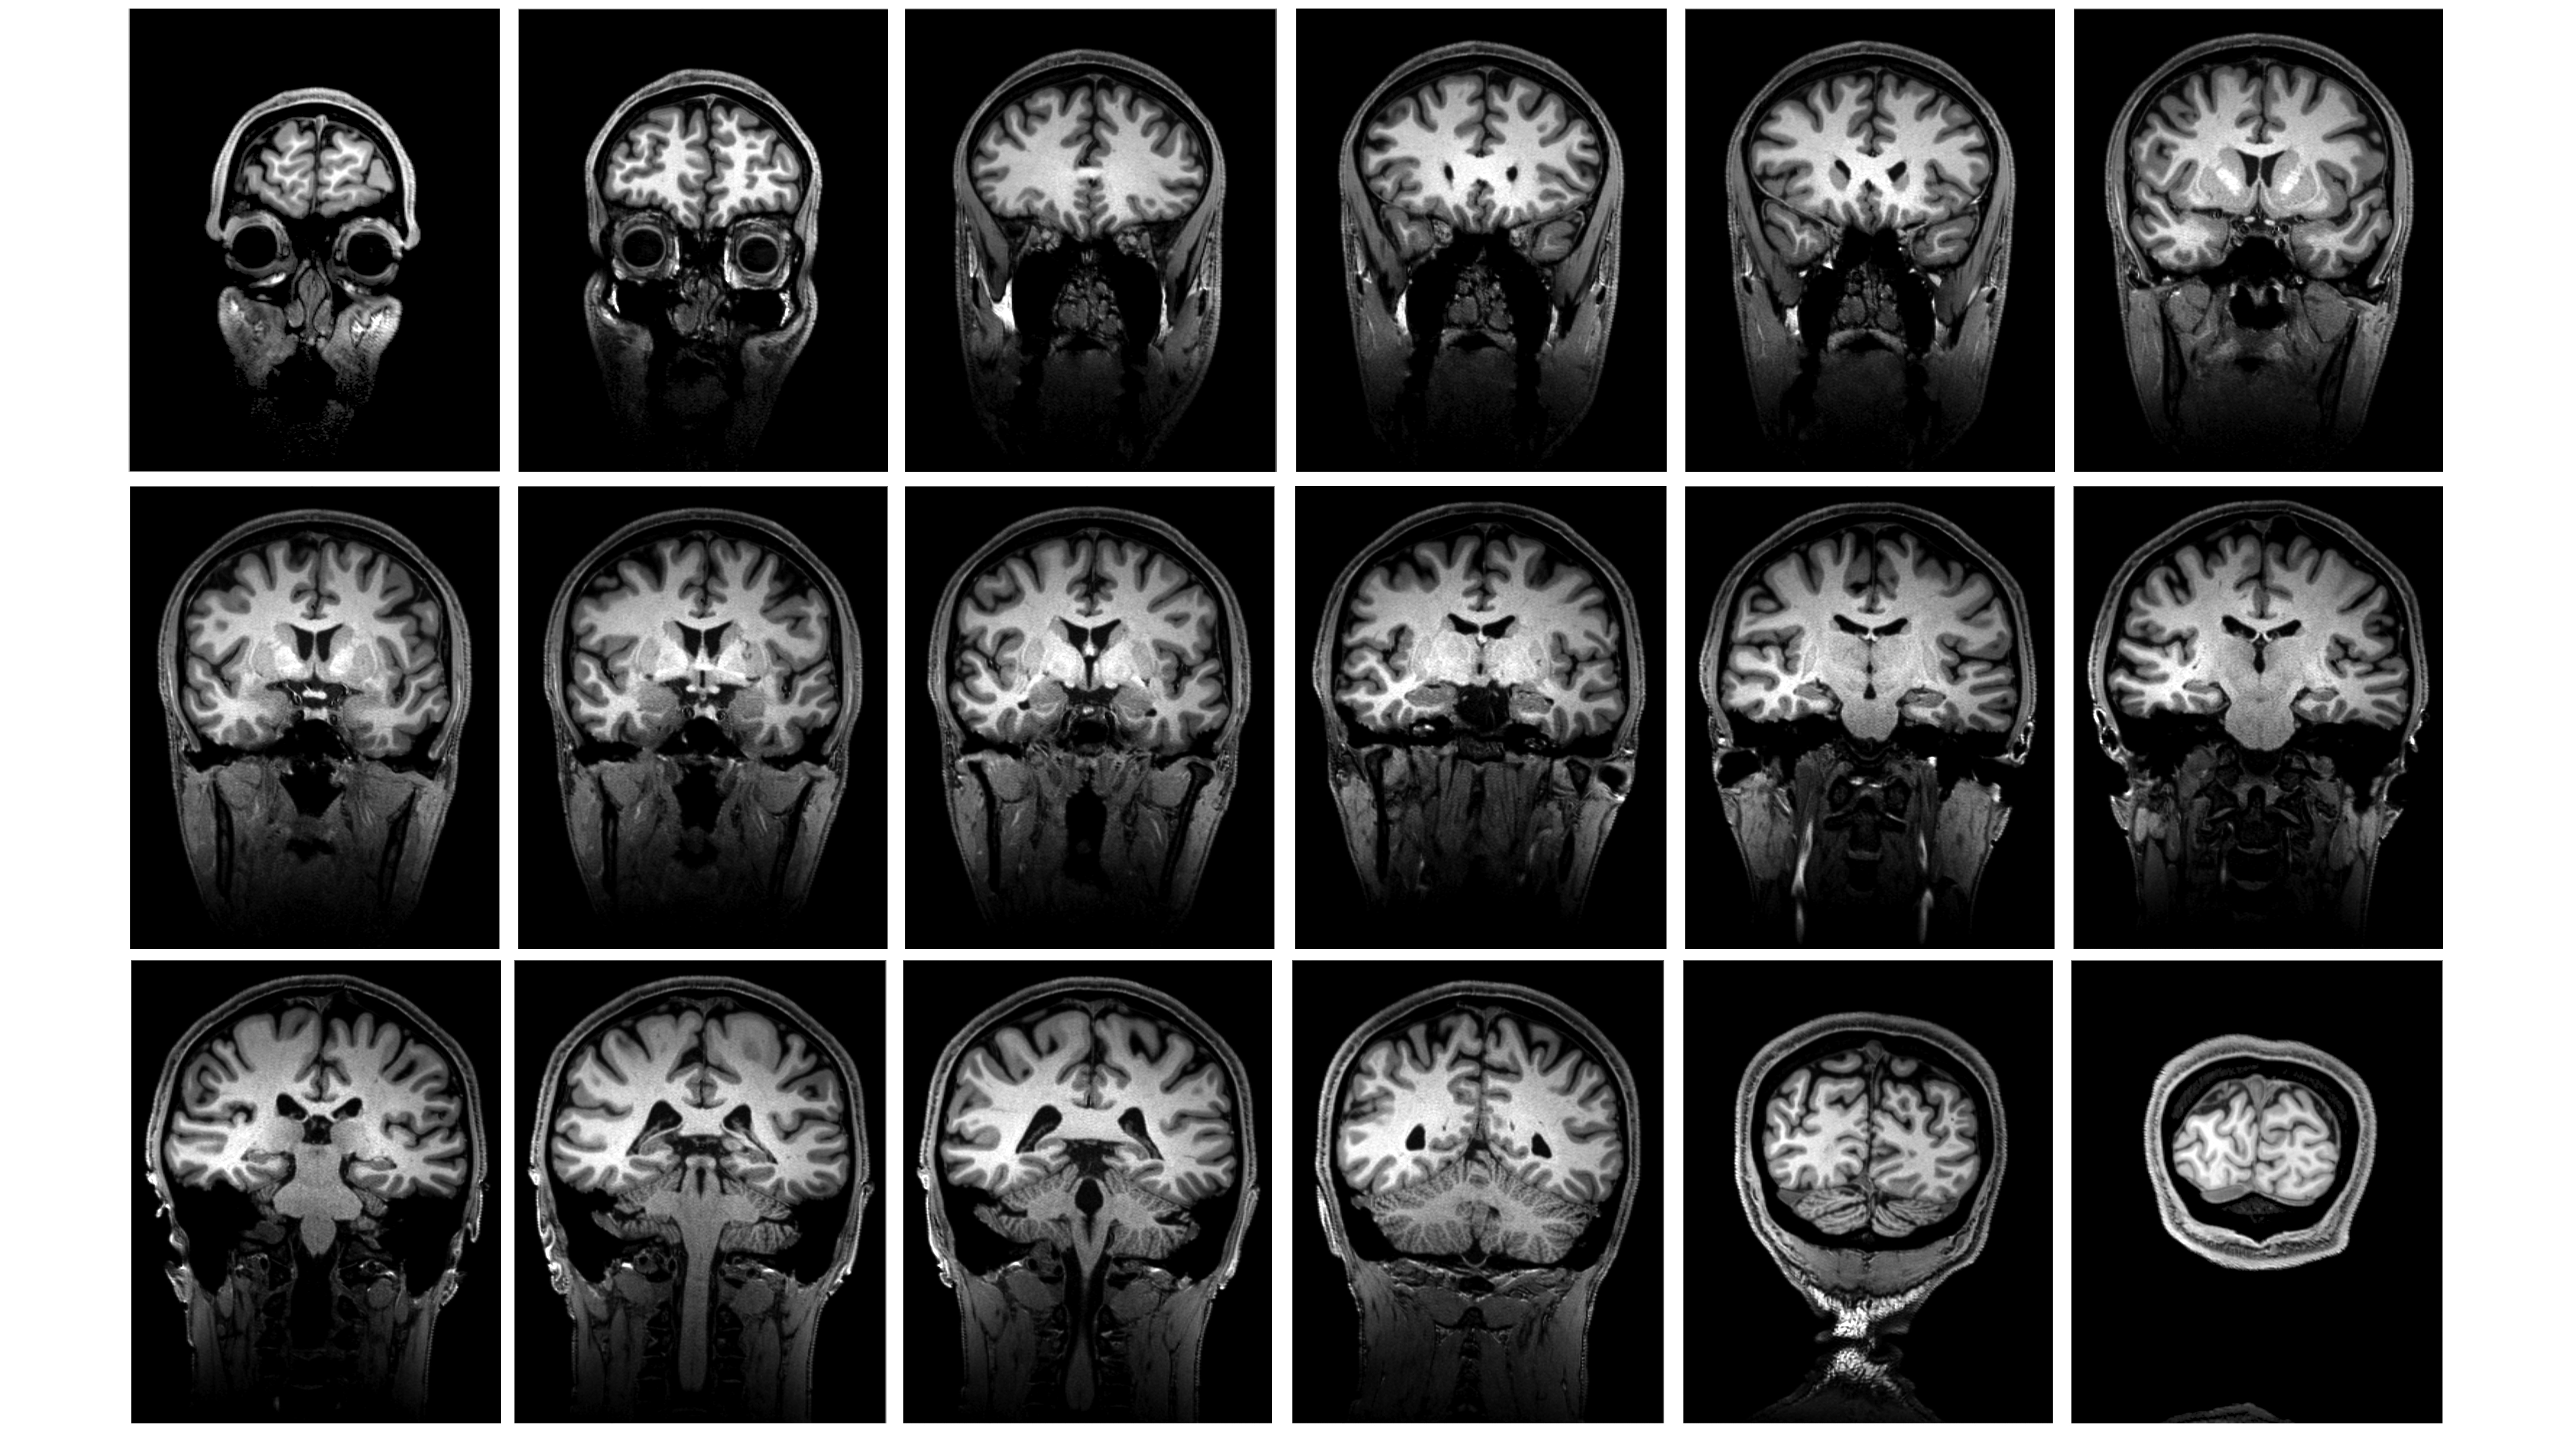

Au cours de cette unité, des travaux pratiques de neuro-anatomie sont organisés pour vous permettre d’appliquer votre savoir à l’aide de pièces anatomiques et d’images radiologiques.

Il est essentiel que vous veniez préparé.e.s à ces TP pour pouvoir en bénéficier au maximum. De plus, l’interactivité rend les TP de 4 heures moins longs et plus enrichissants. N’hésitez donc pas à participer, manipuler les pièces, poser vos questions, et participer aux dissections... À la fin de l’unité, vous devriez être à l’aise en naviguant dans le SNC et capables de mettre en lien l’anatomie des structures avec leur fonction.